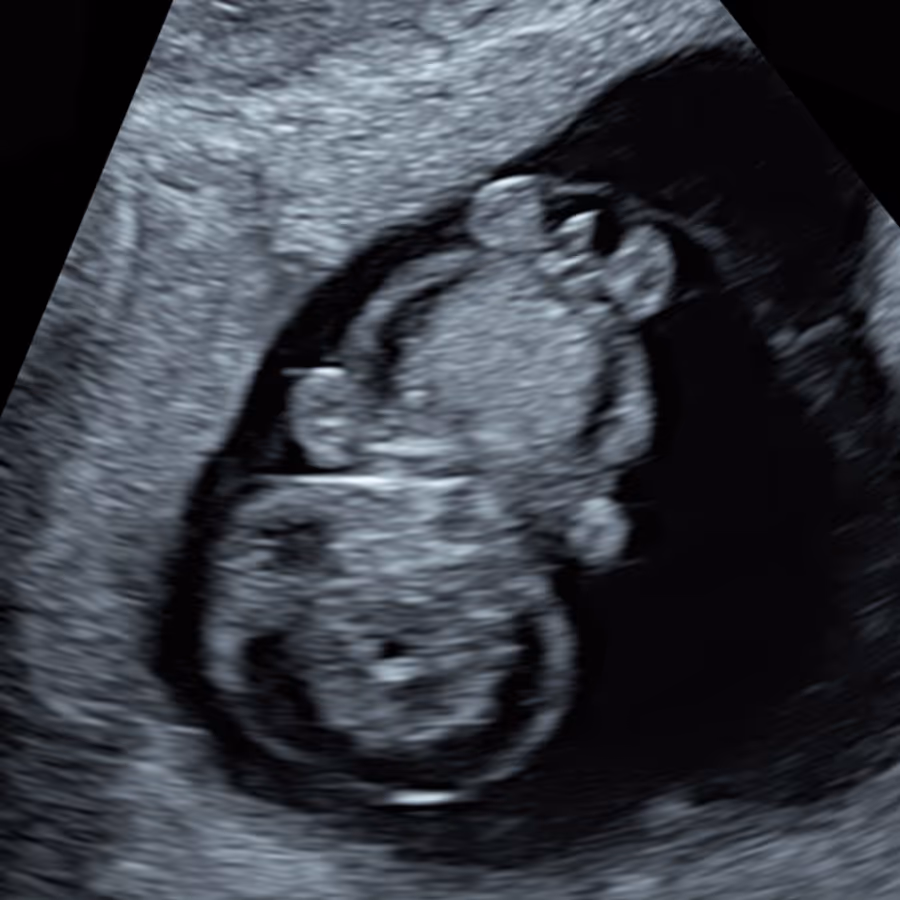

This term is sometimes used by medical professionals to describe an early fetus (10-11 week) with very high NT and generalised skin swelling (oedema). Other terms include "hydropic fetus", "hydropic embryo", or "generalised fetal edema" (oedema). It refers to fetal hydrops - an abnormal build-up of fluid in two or more parts of the baby’s body. Early hydrops usually represents the most severe form of increased NT and is generally associated with a poor outcome, although in some early cases the condition may resolve completely and a healthy baby can be born.